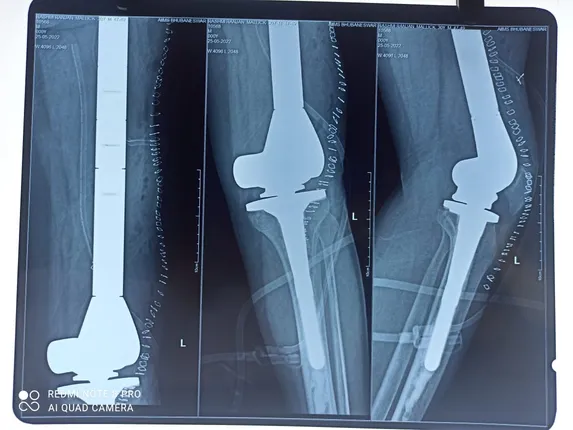

Bhubaneswar: Orthopaedic department of AIIMS Bhubaneswar has performed a total femur replacement which is first in Odisha. A team of Doctors led by Dr Sujit Kumar Tripathy, Additional Professor, Department of Orthopaedics, AIIMS Bhubaneswar has operated a 30-year young man from Kendrapara district who had a huge tumour in the left thigh bone.

The young man subsequently developed recurrence of the tumor and received chemotherapy prior to the current surgery. The tumor was close to the blood vessels. After careful surgery whole of the tumor was excised in toto and total femur megaprosthesis was implanted by Dr Sujit Kumar Tripathy and his team of Orthopaedic department AIIMS Bhubaneswar. The difficult surgery took around four hours.